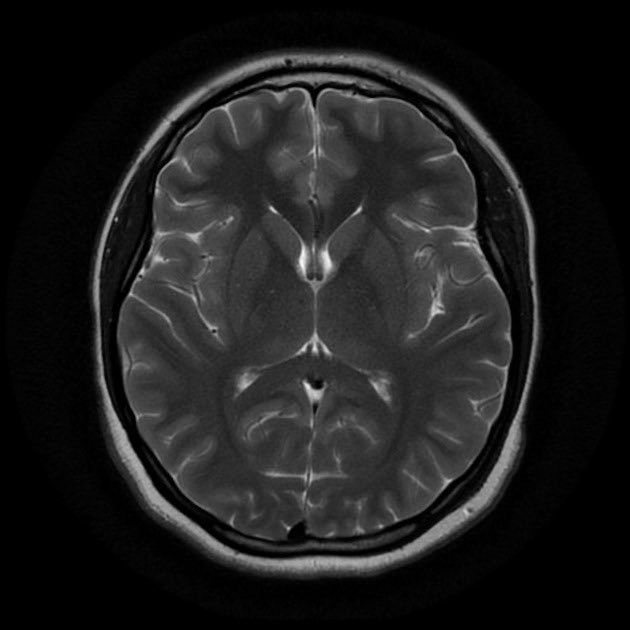

إذا كان المريض يُعاني من هذا الصداع لأول مرة؛ ولأن هذه الأعراض قد تلتبس مع أمراض أكثر خطورة في المُخ والأعصاب

يستلزم أحياناً عمل رنين مغناطيسي للدماغ